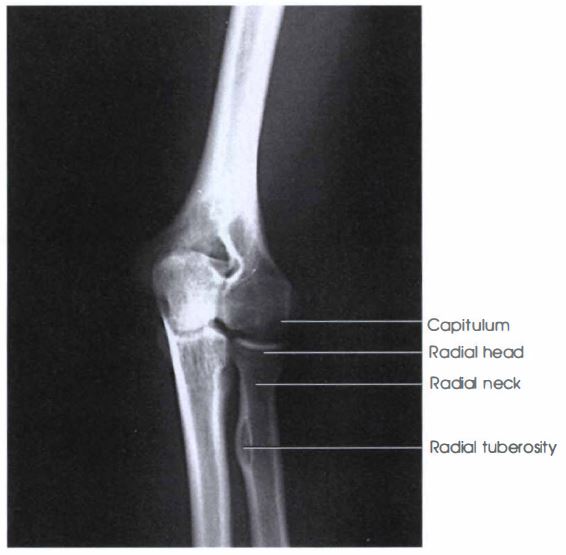

Elbow Xray Positioning Ap Oblique Projection Lateral Rotation